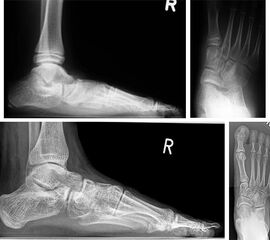

Resektion der Coalitio calcaneonavicularis

Therapeutisch ist bei dieser Form im Kindes- und frühen Jugendlichenalter eine möglichst frühe Resektion direkt nach Diagnosestellung – weitgehend unabhängig vom Ausmaß der Beschwerden – empfehlenswert, da ihre Prognose bei operativer Frühbehandlung besonders günstig ist. In Einzelfällen können inkomplette Brückenbildungen jedoch auch noch im Erwachsenenalter mit gutem Ergebnis reseziert werden 1.

Über einen schrägen Hautschnitt im Verlauf der Hautspaltlinien mit L-förmiger Ablösung des M. extensor digitorum brevis–Ursprunges wird die Coalitio bis in die Tiefe des Pfannenbandes reseziert (Abb. 1) und es werden Anteile des M. extensor digitorum brevis in den etwa 10 mm breiten Resektionsbereich interponiert. Die Länge des Muskel-Interponates reicht zwar in der Regel nicht aus, die gesamte Tiefe des Resektionsspaltes auszufüllen, so daß einige Autoren zu einem Fett-Interponat raten 2; die überwiegend in der Literatur berichteten guten Ergebnisse auch mit Muskel-Interposition können jedoch vom Autor aus eigener Erfahrung bestätigt werden. Bei der Resektion geraten in der Regel gelenkbildende Anteile des lateralen Naviculare-Poles bzw. des vorderen Calcaneus-Abschnittes sowohl im Bereich des Talonavicular-Gelenkes als auch des Calcaneocuboidgelenkes in Wegfall.

Die Ergebnisse der Resektion sind in aller Regel günstig, sofern noch keine sekundären degenerativen Veränderungen insbesondere am Talonavicular-Gelenk eingetreten sind 3. Der Zugewinn an subtalarer Beweglichkeit ist nach ausreichender Resektion in den meisten Fällen deutlich. Die größte bisher publizierte Serie (96 Resektionen mit Interposition von Fettgewebe) wurde von Mubarak et al 2 beschrieben; in 87% trat eine volle Sportfähigkeit postoperativ ein. Besteht zusätzlich eine Deformität, etwa in Form eines Rückfuß-Valgus, so kann z.B. eine Calcaneus-Verschiebeosteotomie hinzugefügt werden.